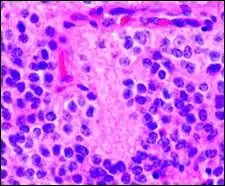

Flexner–Wintersteiner rosettes in Retinoblastoma.

A Flexner–Wintersteiner rosette is a spoke-and-wheel shaped cell formation seen in retinoblastoma and certain other ophthalmic tumors.[3]

Unlike the center of the Homer Wright rosette, the central lumen is devoid of fiber-rich neuropil. The defining feature of this rosette is central extension of cytoplasmic projections of the surrounding cells. Like the Homer Wright rosette, the Flexner–Wintersteiner rosette represents a specific form of tumor differentiation.[5][6][7][8] Electron microscopy reveals that the tumor cells forming the Flexner–Wintersteiner rosette have ultrastructural features of primitive photoreceptor cells.[9] Furthermore, the rosette lumen shows similar staining patterns as in rods and cones,[10] suggesting that Flexner–Wintersteiner rosettes represent a specific form of retinal differentiation. In addition to being a characteristic finding in retinoblastomas, Flexner–Wintersteiner rosettes may also be found in pinealoblastomas and medulloepitheliomas.[5]